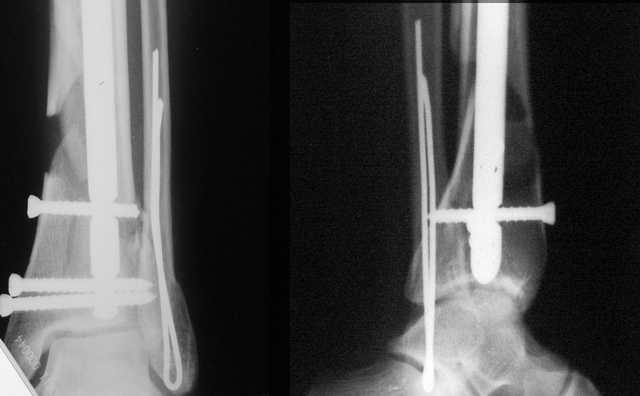

Мы же говорили о проксимальном плече. При переломе tibia, конечно, речи о двух Y-спицах нет. Еще раз о них - пружинящая подвижность без "срезающих" перемещений фрагментов - дополнительный стимул к образованию периостальной мозоли.

А в данном случае - у нас был бы применен locked nail с еще меньшими дырочками на коже и с возможностью полной нагрузки немедленно после операции. Какие тут аргументы в пользу выбора пластины, а не интрамедуллярного гвоздя?

АЧ>Какие тут аргументы в пользу выбора пластины, а не интрамедуллярного гвоздя?

Классически показанием для locked nail яв-ся зоны BC CD, до появления LCP показания к locked nail несколько расширялись в зоны AB и DE

Аргументы: перелом достаточно низкий, трудно будет ввести 3-и блок. винта, а учитывая характер перелома на 2-х дистальных винтах я бы не рекомендовал немедленную полную нагрузку.

С Уважением А.Миронов

Кликните для загрузки файла DSC00841.JPG

42KB (43152 bytes)